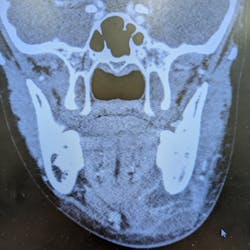

Signs of a facial infection include facial asymmetry in the form of swelling on one side of the face. The face will feel firm, warm, and tender to the touch, and redness of the skin will develop in time. It often starts with dental pain or tooth pain inside the mouth. It can also be pain inside the mouth around the tooth. As it progresses, you may see some intraoral drainage coming from the associated tooth. Infections originating from the skin will often present with external drainage. Severe odontogenic (caused by a bad tooth) infections may even spread and become so large they break through the skin.

There are some spaces around the face, called potential spaces, where the fluid can collect. Some of the spaces inside the jaw and adjacent to the throat can get very dangerous. That’s why it’s important to treat facial abscesses as soon as possible, usually within 24 hours.

The most important concern with any significant facial infection is always going to be the airway. Serious and worrisome signs are when patients have difficulty breathing, difficulty swallowing or pain with swallowing, trouble breathing if they lie flat, or if they have to sit up to breathe. In these situations, the abscess is impinging on the airway.

Significant facial infections that require surgery are taken care of in a hospital setting. The patient is admitted to the hospital, started on IV antibiotics and pain meds, and planned for surgical incision and drainage (commonly called I&D) often within 24 hours, based on the severity and immediate risk of spread. Patients can expect a one- to three-day hospital stay depending on their response, recovery, and need for monitoring. During the hospital stay, the patient remains on antibiotics and pain meds through an IV, both of which will be converted to oral medications upon discharge. Most surgeons also require at least one postoperative visit to check progress.